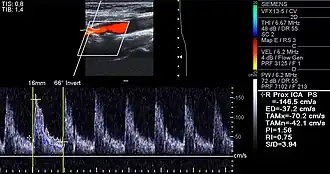

Carotid arteries supply blood to the brain and neck.[25] Marked narrowing of the carotid arteries can present with symptoms such as a feeling of weakness; being unable to think straight; difficulty speaking; dizziness; difficulty in walking or standing up straight; blurred vision; numbness of the face, arms and legs; severe headache; and loss of consciousness. These symptoms are also related to stroke (death of brain cells). Stroke is caused by marked narrowing or closure of arteries going to the brain; lack of adequate blood supply leads to the death of the cells of the affected tissue.[26]

Examples of anatomical detection methods include coronary calcium scoring by CT, carotid IMT (intimal media thickness) measurement by ultrasound, and intravascular imaging techniques, such as intravascular ultrasound (IVUS), and intravascular optical coherence tomography (OCT),[85][86] allowing direct visualization of atherosclerotic plaques.